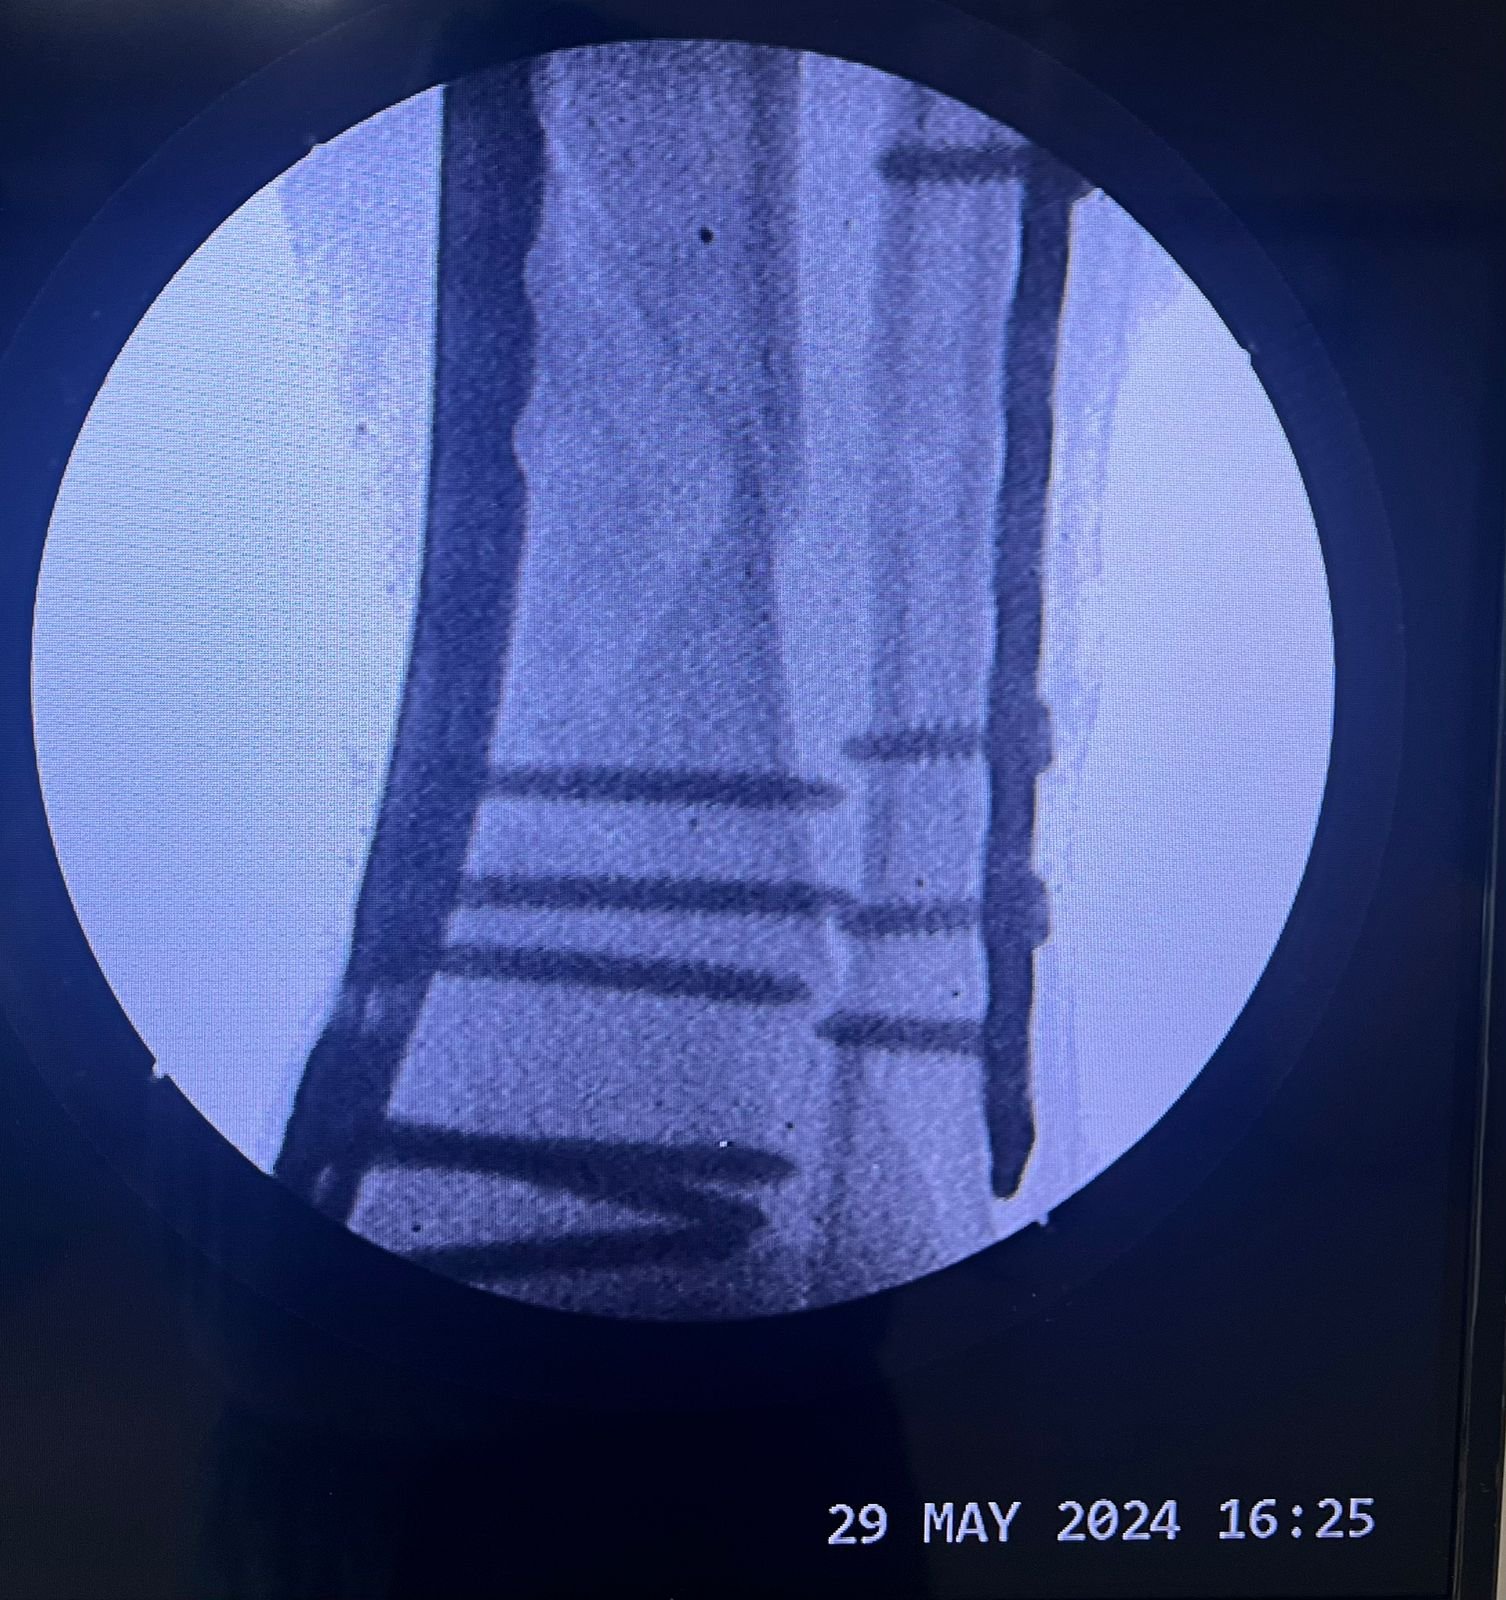

Pre op & postop X-ray compound fracture lower tibia